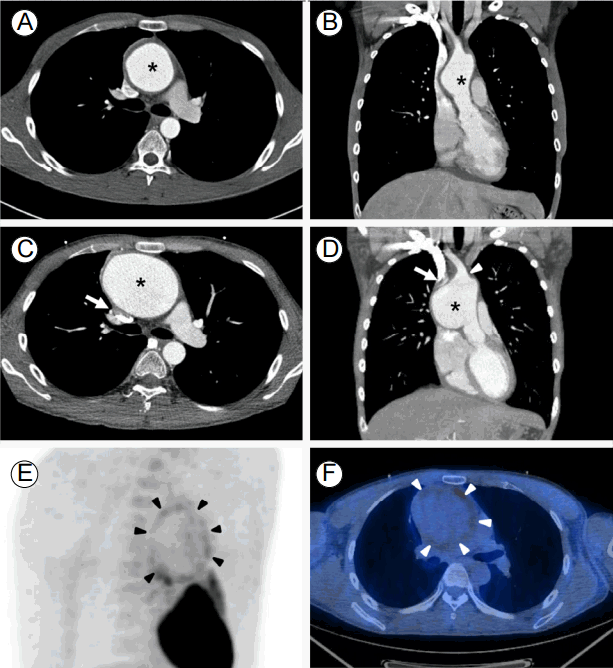

Several months of outpatient follow-up visits went on uneventfully, and the oral steroid dose was reduced with careful monitoring of inflammatory markers. However, the patient complained of chest pain when coughing. Chest computed tomography (CT) revealed concentric wall thickening with a fusiform aneurysm of the ascending thoracic aorta measuring 56 mm in diameter (Fig. 1A and 1B).

Figure 1.

Fusiform aneurysm (*) of the ascending thoracic aorta with concentric wall thickening measuring 56 mm in diameter (A and B). Rapid growth of the aneurysm in a single month. Aneurysm arising from 1.7 cm above the sinotubular junction extending to the origin of the right innominate artery (arrowhead in D). Note the large aneurysm causing extrinsic compression of the superior vena cava (arrows in C and D). This aneurysm was 81 mm in the orthogonal plane (C and D). FDG-PET/CT demonstrating mild diffuse FDG uptake (SUVmax = 2.9) along the aneurysm wall (arrowheads) (E and F). FDG-PET/CT, fluorodeoxyglucose-positron emission tomography/computed tomography; SUV, standardized uptake value.

The patient was referred to our hospital for surgical repair of the aortic aneurysm. Elective surgery was planned, and he underwent a routine work-up for open ascending aorta replacement. Although the patient’s erythrocyte sedimentation rate was moderately elevated at 55 mm/h (reference range, 0-22 mm/h), his C-reactive protein level was low at 0.3 mg/dL (reference range, 0-0.3 mg/dL). Assuming that inflammation due to relapsing polychondritis was under control, oral steroid therapy was continued with a plan to change to intravenous stress doses during admission for surgery. However, CT angiography revealed rapid growth of the aneurysm to 81 mm in a single month (Fig. 1C and 1D). Transthoracic echocardiography revealed an intact aortic root without aortic valve regurgitation. Fluorodeoxyglucose (FDG)-positron emission tomography (PET)/CT demonstrated increased uptake of the aneurysm wall, which raised suspicion of active aortitis (Fig. 1E and 1F). Except for the aortic aneurysm, no significant organ uptake was present in the FDG-PET/CT scan.